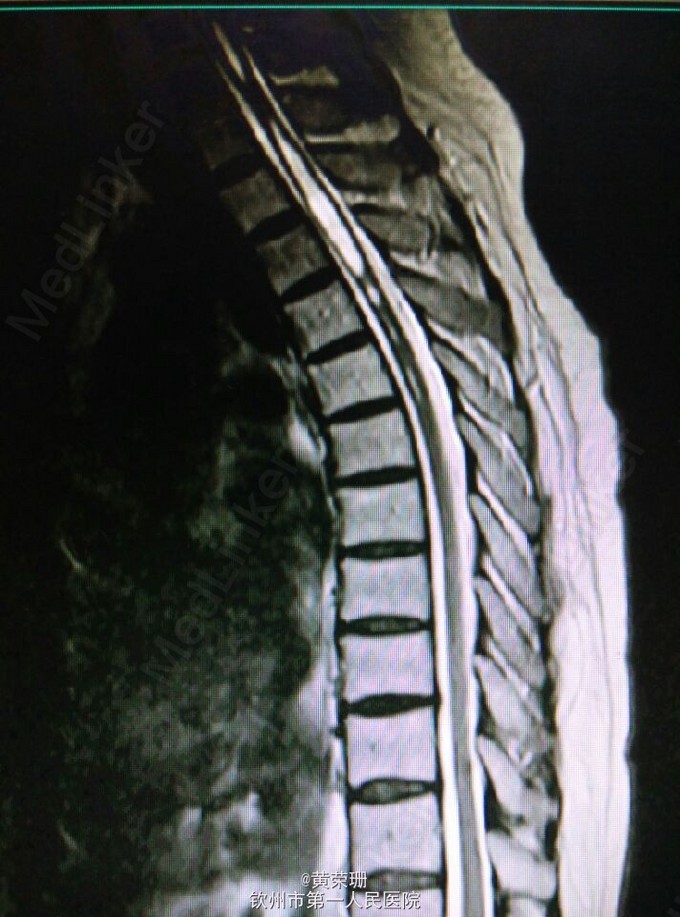

脊髓空洞症1例

黄医师   钦州市第一人民医院

52岁女性患者,既往有颈椎病史。诉反复头晕1月余,伴晕眩,平卧后起立时明显。查体:神清,言清,双上肢、下颌部浅感觉减退,右侧明显,双上肢腱反射(++),双下肢腱反射(+),肌力5级,肌张力正常。入院后行头颅+颈椎MRI发现脊髓空洞症。